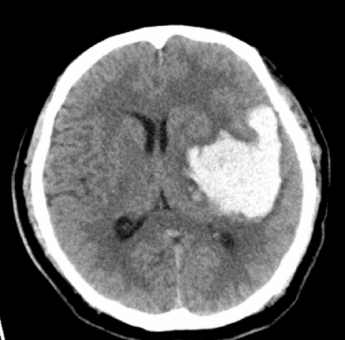

CT的影像让大家一惊 , 脑出血 ,巨大的血肿已经造成了中线的移位、一侧侧脑室的受压 。

“这个病人刚刚出现的状态我们叫脑疝 ,是神经重症最为危重的状态之一 , 如果不及时处理 , 会造成很严重的后果 , 导致脑死亡或者病人的死亡 。

脑疝的形成是由于颅内局部或全部的压力增高 , 比如肿瘤、出血、大面积的脑梗塞、外伤等 ,造成脑组织移位并被挤进硬脑膜裂隙或枕骨大孔中 , 并压迫脑干、脑神经和血管及阻塞脑脊液循环 , 产生一系列紧急症状 。

脑疝是脑水肿、颅内压增高的严重后果 , 脑疝又反过来加重脑水肿、颅内压增高 , 从而形成恶性循环 。

病人出现脑疝的时候 , 常常会有呼吸 , 心率以及血压的异常 , 也可以出现瞳孔的变动 , 这些其实是大脑在向我们预警-----你看这张片子像不像一张既愤怒又沮丧的脸?